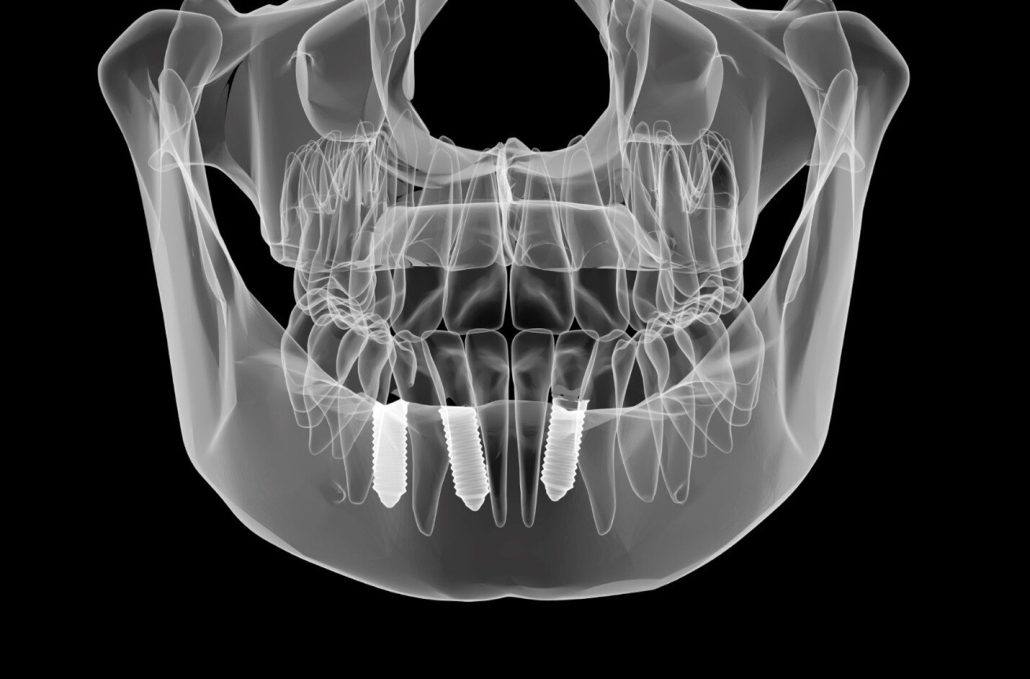

تصویربرداری دیجیتال (Intraoral X-ray): به عنوان یکی از روش های رادیولوژی فک و دندان برای ارزیابی وضعیت ایمپلنت، کنترل سطح استخوان و تشخیص عوارض خفیف کاربرد دارد.

CBCT (Cone Beam Computed Tomography): ارائه تصویر سه بعدی دقیق از استخوان فک و موقعیت ایمپلنت، امکان تشخیص مشکلات پیچیده یا تحلیل استخوان در مراحل اولیه را فراهم می کند.

مزایای تصویربرداری پیشرفته: تشخیص زودهنگام مشکلاتی که هنوز علامت بالینی ندارند، به دندانپزشک اجازه می دهد برنامه پیشگیرانه یا درمان اصلاحی را سریع اجرا کند.

ثبت و مقایسه دوره ای: تصاویر دیجیتال به صورت فایل آرشیو شده ثبت می شوند و در مراجعات بعدی، مقایسه تغییرات بافت نرم و استخوان، روند مراقبت را بهینه می کند و جهت نگهداری از ایمپلنت بسیار کاربردی هستند.